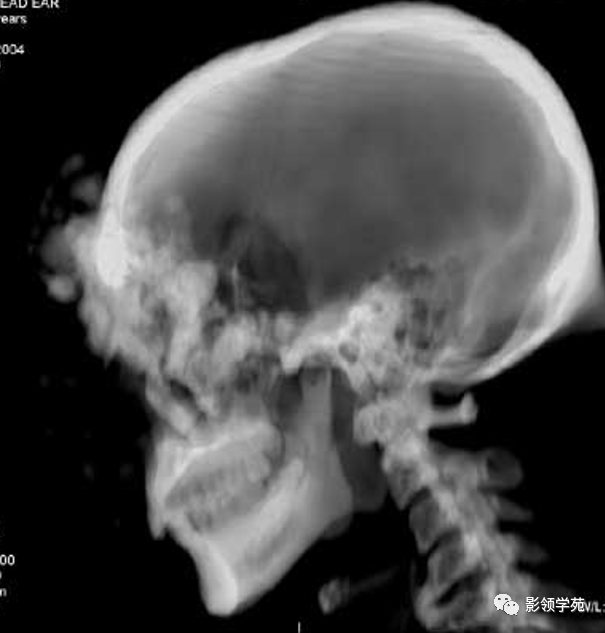

额骨骨纤维肉瘤并肺部转移